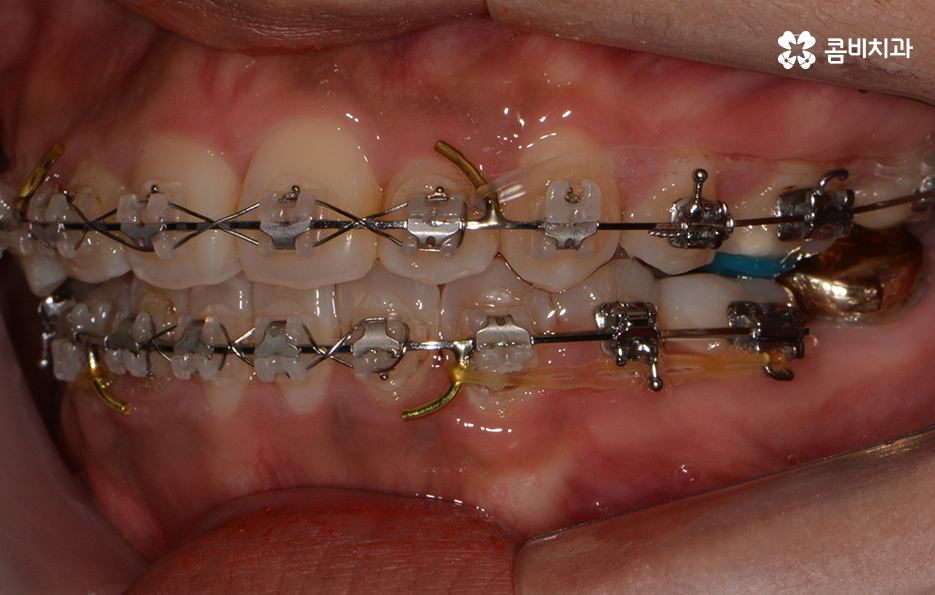

교정이 시작된 후 경과 - 발치를 했던 부위의 치아 사이 빈 공간이 사라짐